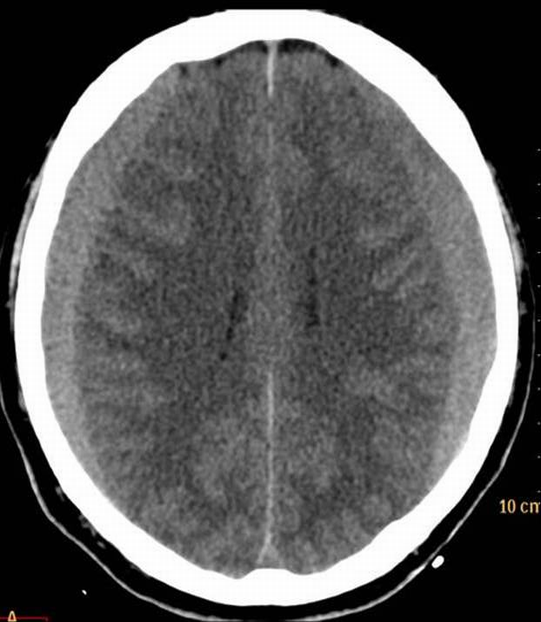

The key question whether the patient ha intracranial hematoma, which causes mass effect and later leads to vasoconstriction. In the presence of open skull fracture signed by liquorrhea severe infection and herniation might occur. To exclude intracranial hemorrhage CT is the modality of choice.

All three types of intracranial hematoma can occur as a result of head trauma:

• Hydrocephalus is diagnosed by the radiologist, the site of the obstruction and signs of progression should also be reported. Unenhanced CT is the basic imaging modality in hydrocephalus, nevertheless MRI provides more detailed information on CNS lesions.